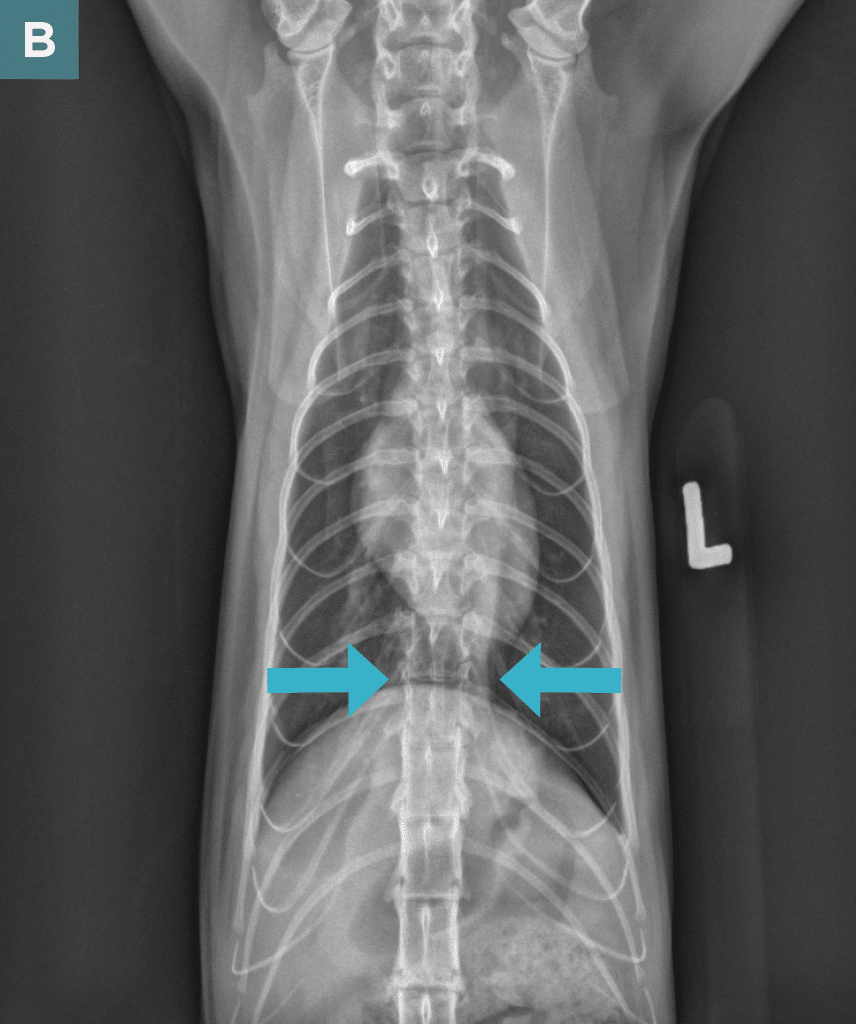

On survey thoracic radiographs, the heart and lungs were normal. A soft tissue opacity in broad-based contact with the diaphragm was noted in the caudal thorax (FIGURE 2), and the intra-abdominal portion of the stomach was shifted slightly cranially and to the left; findings were consistent with a hiatal hernia. The cat was anesthetized for computed tomography (CT) of the head and possible surgery.